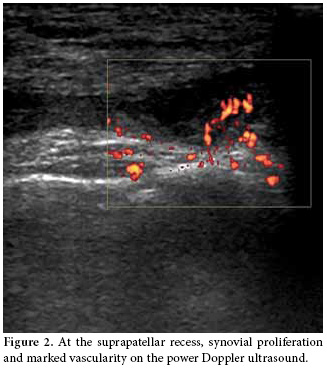

The US examination was performed first with the patient in a supine position in which the knee is flexed approximately 20-30 degrees while supported by a pillow, and the transducer was positioned longitudinally above the patella at the level of suprapatellar recess. The total synovial thickness and anteroposterior diameter of the suprapatellar bursa were measured. The synovial proliferation was considered positive when the total synovial thickness was above 3 mm, and the effusion was considered positive when it was 5 mm or higher (Figure 1a, b). During the longitudinal scan at the level of the suprapatellar recess, special attention was paid not to compress the recess. In the evaluation of the synovial proliferation, any presence of vascularization as a supporting evidence was evaluated with the color mode of the power Doppler US (Figure 2). However, because the study aimed to compare the B mode US findings and MRI findings and no contrast material was used in the MRI evaluations, spectral analyses and/or comparisons could not be made. In the same position, the patellar and quadriceps tendons were examined, and tendonitis was diagnosed if the thickness was increased and blurring and heterogeneous hypoechogenecity were differentiated.